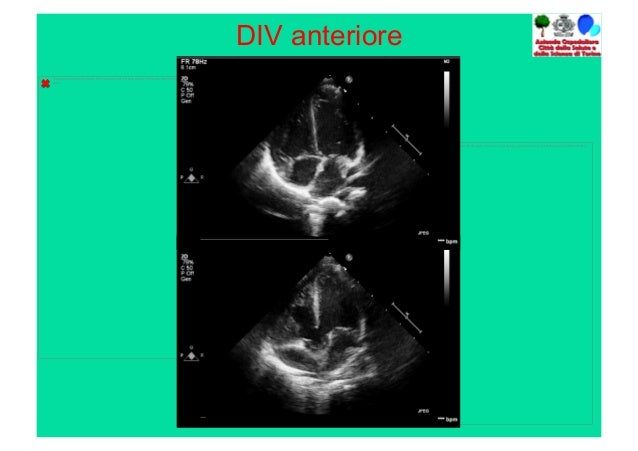

B Difetti Settali Semplici Corso Le Immagini Del Cuore